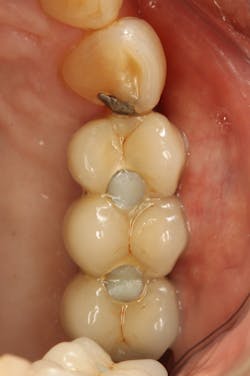

Loss of interdental papilla after extraction can be compensated for with pink porcelain when adjacent implants are splinted. Also, splinting can simplify clinical procedures and enhance esthetics (figure 4).

Figure 4: Esthetic considerations